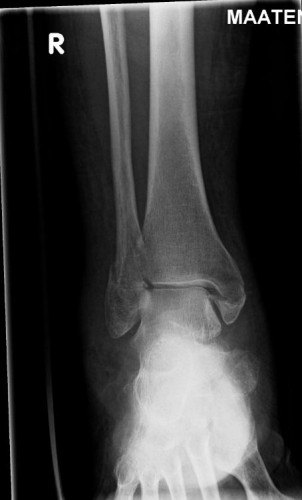

X-ray image of a fractured ankle. (Credit: Heikki Kröger)